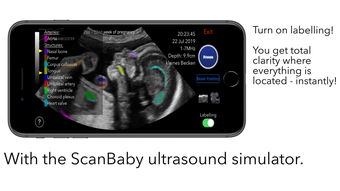

The app is divided into three different modes: Scan, Learn, and Watch. In Scan mode, users can scan a baby with labelling mode turned on to see all the important structures colored. This helps expecting parents understand the shown structures better and compare the ScanBaby image to their own ultrasound image. In Learn mode, users are taught about the developmental stages of their child through artfully crafted 3D scans of real babies that can be moved around. The scans come with labelling as well. Finally, in Watch mode, the app includes many different ultrasound videos that users might see during their own examination, with a short explanation of what can be seen.